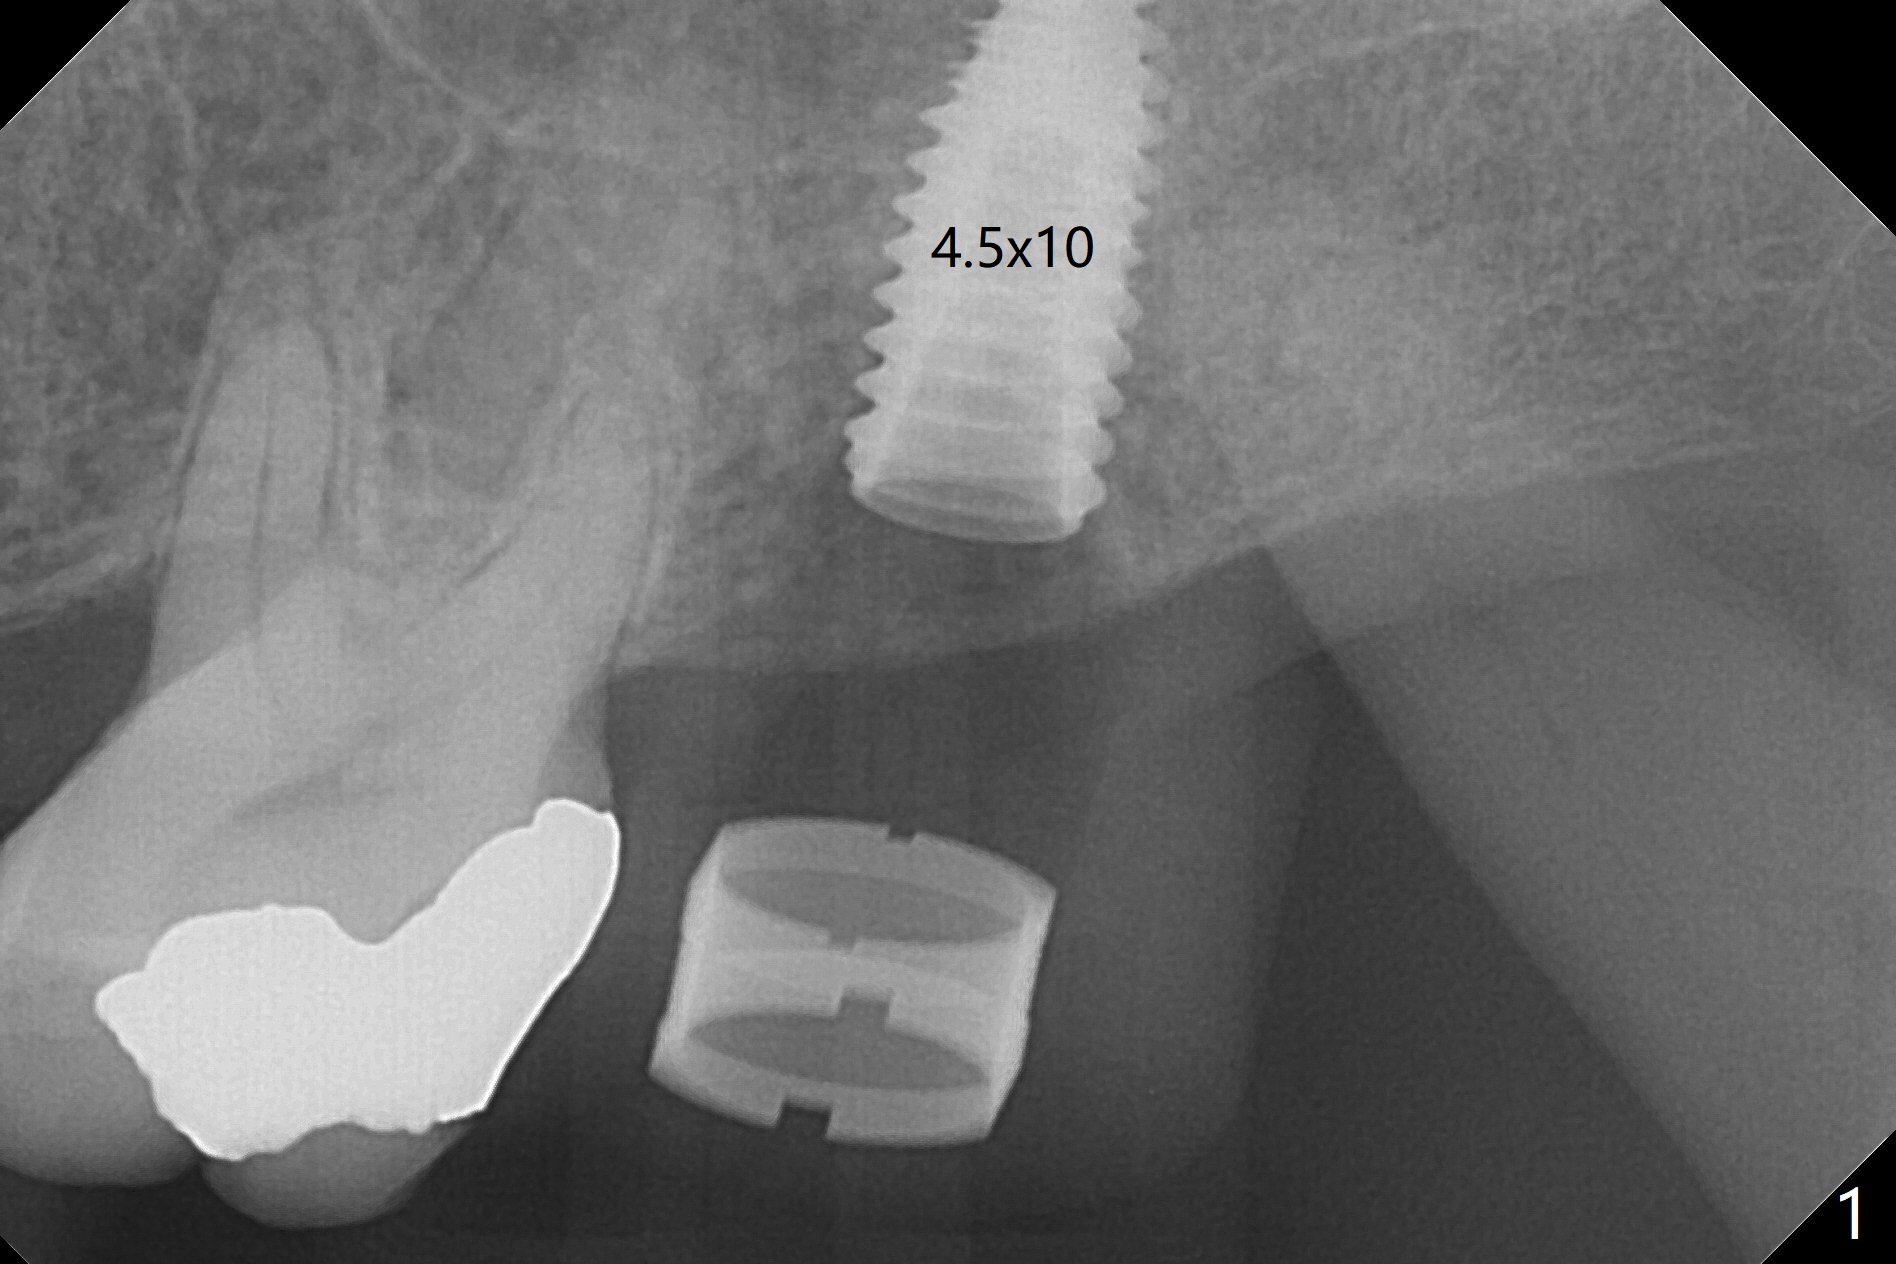

After extraction at #15 with 9 mm offset, a 12 mm bone trimmer is used to create a dimple in the septum. When a 4x7.3 mm drill is done according to drill sequence, initial osteotomy has no palatal wall. A 4.5x10 mm dummy implant cannot engage for sinus lift. DIO Sinus Approaching drill cannot enter IS green metal sleeve. When a 4x8.5 mm drill is finished, the sinus floor is intact. This is not the case when a 2.2x10 mm drill is used. Water membrane lifter does not seal the osteotomy (palatal defect). The 4.5x10 mm dummy implant is used for sinus lift, followed by 2-3 Amalgam carriers of allograft lifted with the same implant (Fig.1,2). After 4x10 mm drill and 2-3 carriers of Vanilla graft, a 5x11.5 mm implant is placed >55 Ncm with immediate placement of a 5.7x4(2) mm abutment (Fig.3). With sticky bone and 2 pieces of PRF in the remaining socket, an immediate provisional is fabricated and seated. When the patient returns for impression nearly 6 months postop, she feels mild pain. In fact the temporary crown/abutment is loose and traps food underneath with the erythematous gingival cuff. A 5.7x4(3) mm abutment is placed and torqued without gap for impression (no temp); the implant threads are exposed distal (Fig.4 <). Retrospectively, the incompletely seated cemented abutment should be tightened ~ 1 month postop when the socket heals.